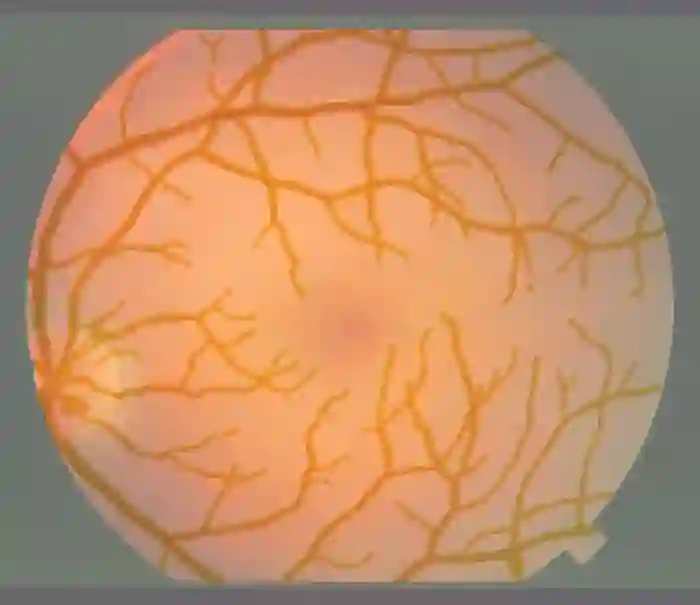

Image segmentation is a fundamental task in image analysis and clinical practice. The current state-of-the-art techniques are based on U-shape type encoder-decoder networks with skip connections, called U-Net. Despite the powerful performance reported by existing U-Net type networks, they suffer from several major limitations. Issues include the hard coding of the receptive field size, compromising the performance and computational cost, as well as the fact that they do not account for inherent noise in the data. They have problems associated with discrete layers, and do not offer any theoretical underpinning. In this work we introduce continuous U-Net, a novel family of networks for image segmentation. Firstly, continuous U-Net is a continuous deep neural network that introduces new dynamic blocks modelled by second order ordinary differential equations. Secondly, we provide theoretical guarantees for our network demonstrating faster convergence, higher robustness and less sensitivity to noise. Thirdly, we derive qualitative measures to tailor-made segmentation tasks. We demonstrate, through extensive numerical and visual results, that our model outperforms existing U-Net blocks for several medical image segmentation benchmarking datasets.

翻译:图像分割是图像分析和临床实践的一项基本任务。 目前的最先进的技术基于U- shape 类型编码器- 编码器网络,称为U- Net。 尽管现有的 U-Net 类型网络报告了强大的性能,但它们受到若干重大限制。 问题包括: 接收字段大小的硬编码, 影响性能和计算成本, 以及它们没有考虑到数据中固有的噪音。 它们与离散层有问题, 没有提供任何理论依据。 在这项工作中, 我们引入了连续的 U- Net, 一个图像分割网络的新组合。 首先, 持续的 U- Net是一个连续的深神经网络, 以第二顺序普通差异方程式为模型, 引入新的动态区块。 第二, 我们为我们的网络提供理论保证, 显示更快的趋同性、 更高强度和较少对噪音的敏感度。 第三, 我们通过广泛的数字和视觉结果, 我们通过模型超越了现有的一些医学图像分割基准数据集的 U-Net 。